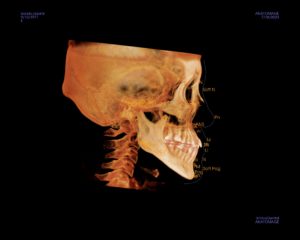

CT撮影

歯や顎の骨の状態を確認します。

セファロ分析では規格にそって撮影された患者さんの頭部のレントゲンをトレースし、

様々な計測点・平面の角度などから得られた数値を、いくつかの基準値と比較することで

診断・治療計画の立案を行っています。